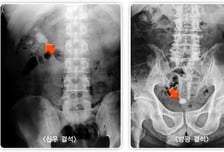

'출산의 고통만큼 극심한 통증'으로 응급실에 실려 와야 하는 병이 있다. 바로 '요로결석'이다. 땀을 많이 흘리는 여름철에 가장 흔한데, 건강보험심사평가원에 따르면 2023년 요로결석으로 병원을 찾은 환자(33만5628명) 가운데 7월(4만4419명)과 8월(4만8468명)에 가장 많았다. 2021년과 2022년에도 각각 7·8월이 그 해의 최대 환자 수를 기록했다. 요로결석은 콩팥·요관·방광·요도 등 '소변이 지나가는 길'에 돌이 생기는 질환이다. 한 번 발생하면 재발 위험이 높고, 출산의 고통에 빗댈 만큼 극심한 통증을 유발해, 예방과 빠른 대처가 중요하다. 인천힘찬종합병원 비뇨의학과 이장희 과장은 "여름철에는 땀 배출이 많아 체내 수분이 부족해지면서 소변량이 줄고, 소변이 농축돼 결석이 형성되기 쉬운 환경"이라며 "통증은 결석이 막는 위치에 따라 다양하게 나타나는데, 옆구리·복부 통증이 심하고, 혈뇨가 나오기도 한다"고 말했다. ━통증 방치했다간 콩팥 망가질 수 있어 ━여름에는